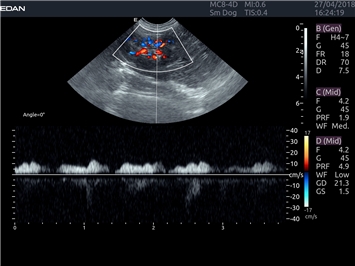

EDAN Acclarix LX4 VET

EDAN Acclarix LX4 VET представляет собой профессиональную ультразвуковую систему, специально разработанную для ветеринарных исследований. Сочетание стабильности, высокой производительности и эффективности делает эту систему идеальным выбором для современной ветеринарной практики.

Импульсно-волновой допплер:

Да

Триплексное сканирование:

Дуплексное сканирование: